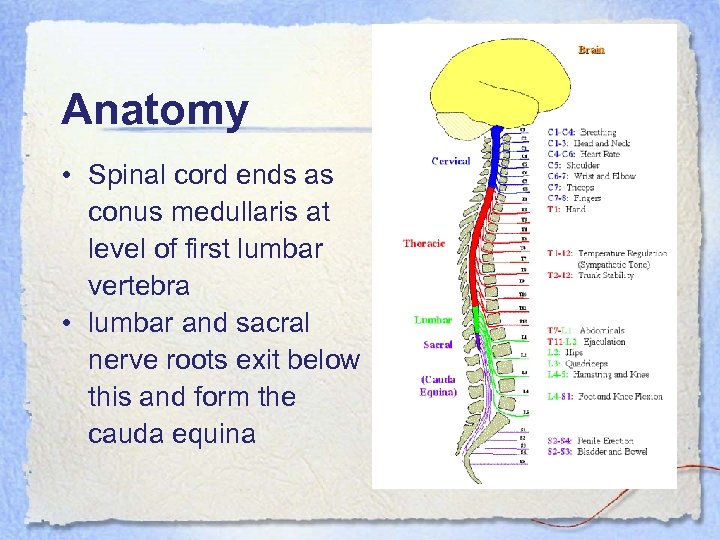

Anatomy • Spinal cord ends as conus medullaris at level of first lumbar vertebra • lumbar and sacral nerve roots exit below this and form the cauda equina

Anatomy • Spinal cord ends as conus medullaris at level of first lumbar vertebra • lumbar and sacral nerve roots exit below this and form the cauda equina